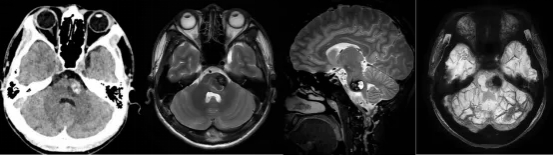

就医后,头颅CT和磁共振检查结果显示,他的脑干“桥脑左侧异常信号灶,考虑海绵状血管瘤且合并出血”。

术前影像